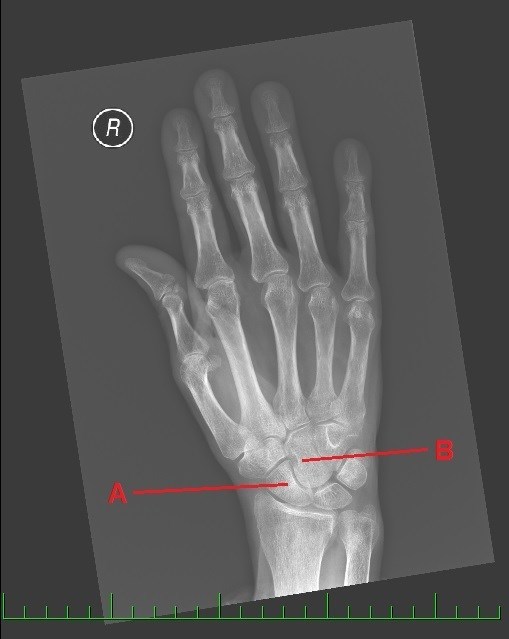

A dál co potřebujete k získání finálních souřadnic? Trocha z té zdravotnické praxe. Správný geokačer má silně vyvinutý smysl pro všímání si detailů, skrytých souvislostí a tak podobně. Princip je jednoduchý. Nepůjde o žádnou kdoví jak složitou matematickou šifru s IT podtextem. V budoucích několika minutách, hodinách či dnech se z Vás stanou radiologové (lékaři zabývající se zobrazovacími technikami) a anatomové. Tak Vás jistě nepřekvapí několik obrázků, na kterých bude vyznačen útvar, který musíte poznat a latinsky (pokud jiným jazykem, tak Vás na to upozorním) pojmenovat. Myslím, že vše bude jasné. Tak jdeme na to…

A - počet písmen v názvu útvaru (latinsky, 2 slova)

B - počet písmen v názvu útvaru (latinsky, 2 slova)